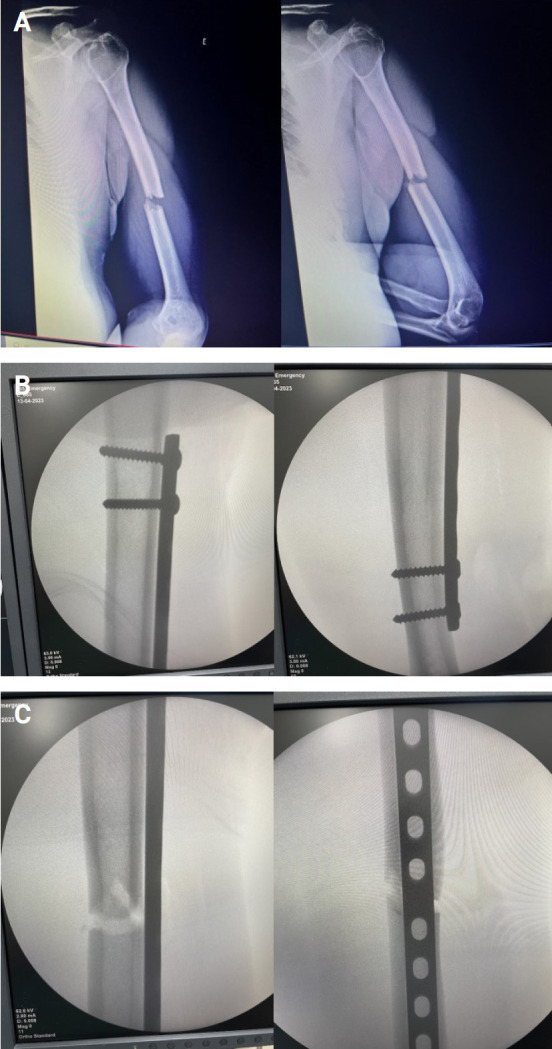

Methods: A prospective cohort study included 43 patients who underwent anterior bridge plating with MIPO for closed, displaced humeral shaft fractures. Forty patients had full follow-up (functional and radiological) and three patients were lost to follow-up. Fractures were classified using the AO classification system. Surgical technique involved incision, reduction, and fixation with locking compression plates. Follow-up assessments were conducted at various intervals, and functional outcomes were evaluated.

Abstract Image